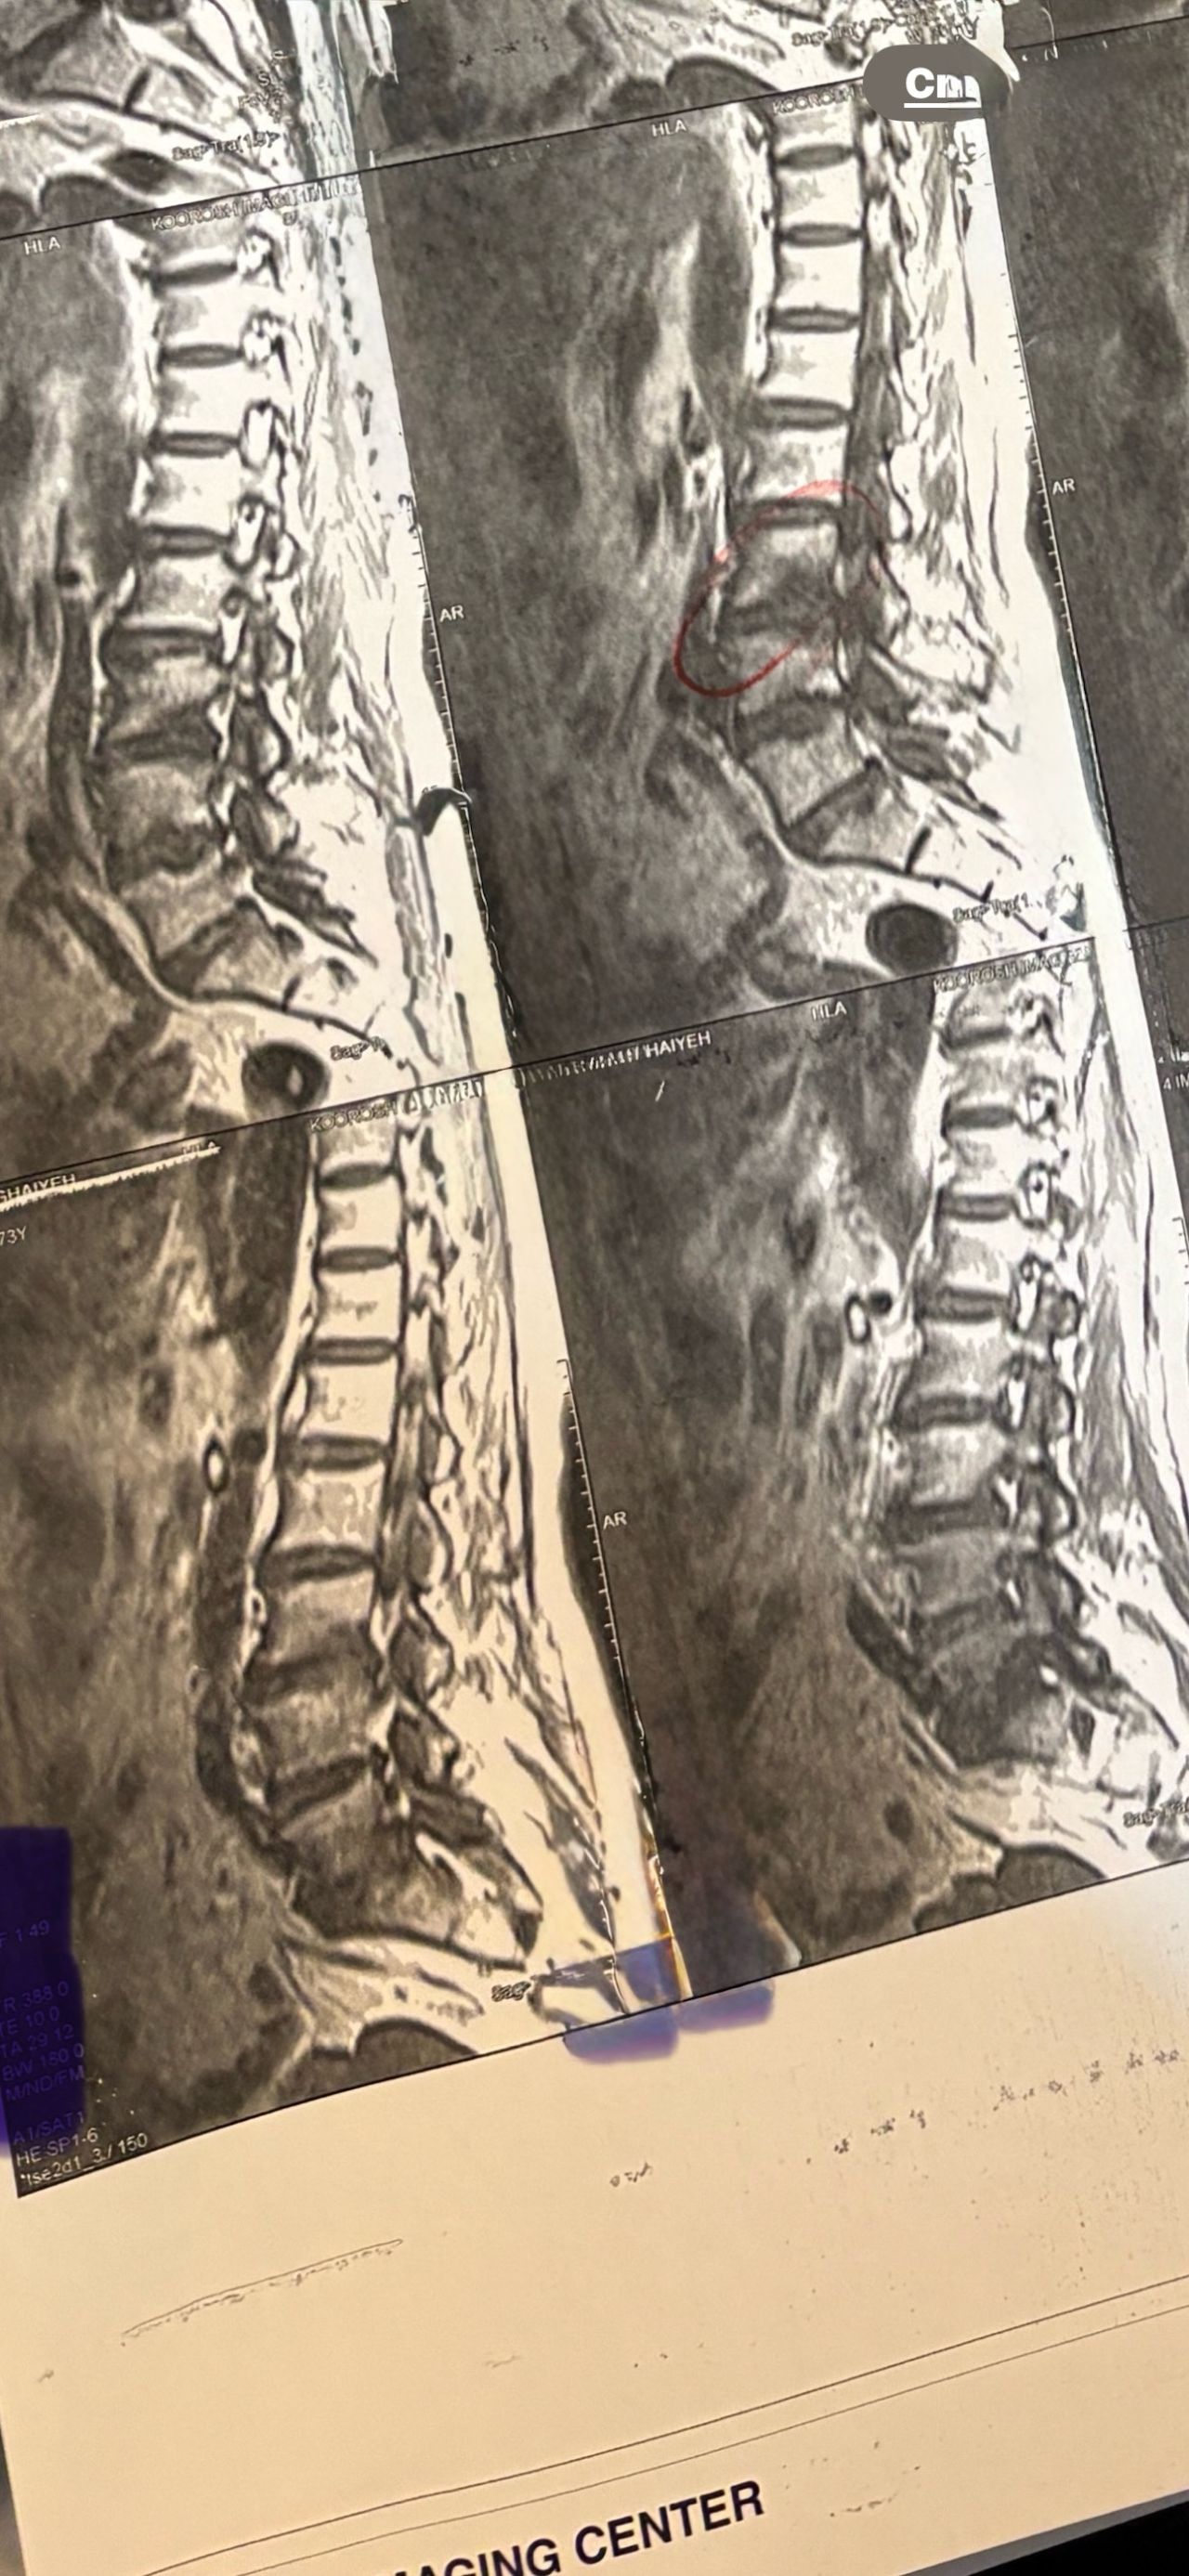

41 years old man presented to my clinic in October 2023 with acute and sever R neck pain with radicular pain to his R upper extremity along C6 dematom since 2 weeks ago. Examination didn’t show any upper motor signs. Was suggested urgent surgery

I ordered EMG/ NCV : showed mild R C6, C7 irritation without any active axonal loss

In his MRI was reported R. para R. IVF Massive extrusion. I decided to control his pain and manage this patient with reevaluation of patient every other session. For 5 sessions i just used acupuncture and laser and IFC and mild adjustments to his R. T3-T7 and mild arthosteem to above and below involved segment. Cervical adjustment considered contraindicated for this patient. From session 6th- 8th i started to use mild/gentle cervical decompression. He used soft cervical collar all the time. His pain decreased by 80 percent

I gave him cervical traction pump to be used 3-5 times per day at home for the next 3 months and i released the patient. He was evaluated every week once for one month and after that every 2 weeks. After 3 month I repeated MRI. Size of the herniated disc was reduced greater than 50 percent. Asked him to do another mri in 6 months

In general: Precise selection of the patients, examination,diagnosis, plan of management, reevaluation and treatment can be done by doctors of chiropractic for the patients with spinal disc herniation and stenosis Moreover giving reasonable time to these kind of patients under direct supervision by their chiropractic doctors can prevent unnecessary surgery. Proper selection of these kind of patients is another important fact that can be done precisely by chiropractors.

MRIs before and after proper management of this patient: